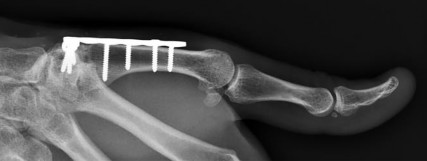

Question 19:

A 65-year-old female underwent volar locked plating for a comminuted distal radius fracture 6 months ago. The fracture has healed uneventfully. However, she now presents to the clinic with a sudden inability to actively flex the interphalangeal (IP) joint of her thumb. Which of the following technical errors during the index surgery most likely caused this complication?

Correct Answer: Placement of the volar plate distal to the watershed line

Explanation:

The patient is presenting with a spontaneous rupture of the Flexor Pollicis Longus (FPL) tendon, which is a well-documented complication of volar plating of the distal radius. It is most commonly caused by iatrogenic plate prominence due to placement of the plate distal to the 'watershed line'. This creates attrition and friction on the FPL tendon as it glides over the prominent hardware, eventually leading to rupture. Prominent dorsal screws would endanger the extensor tendons (e.g., EPL).